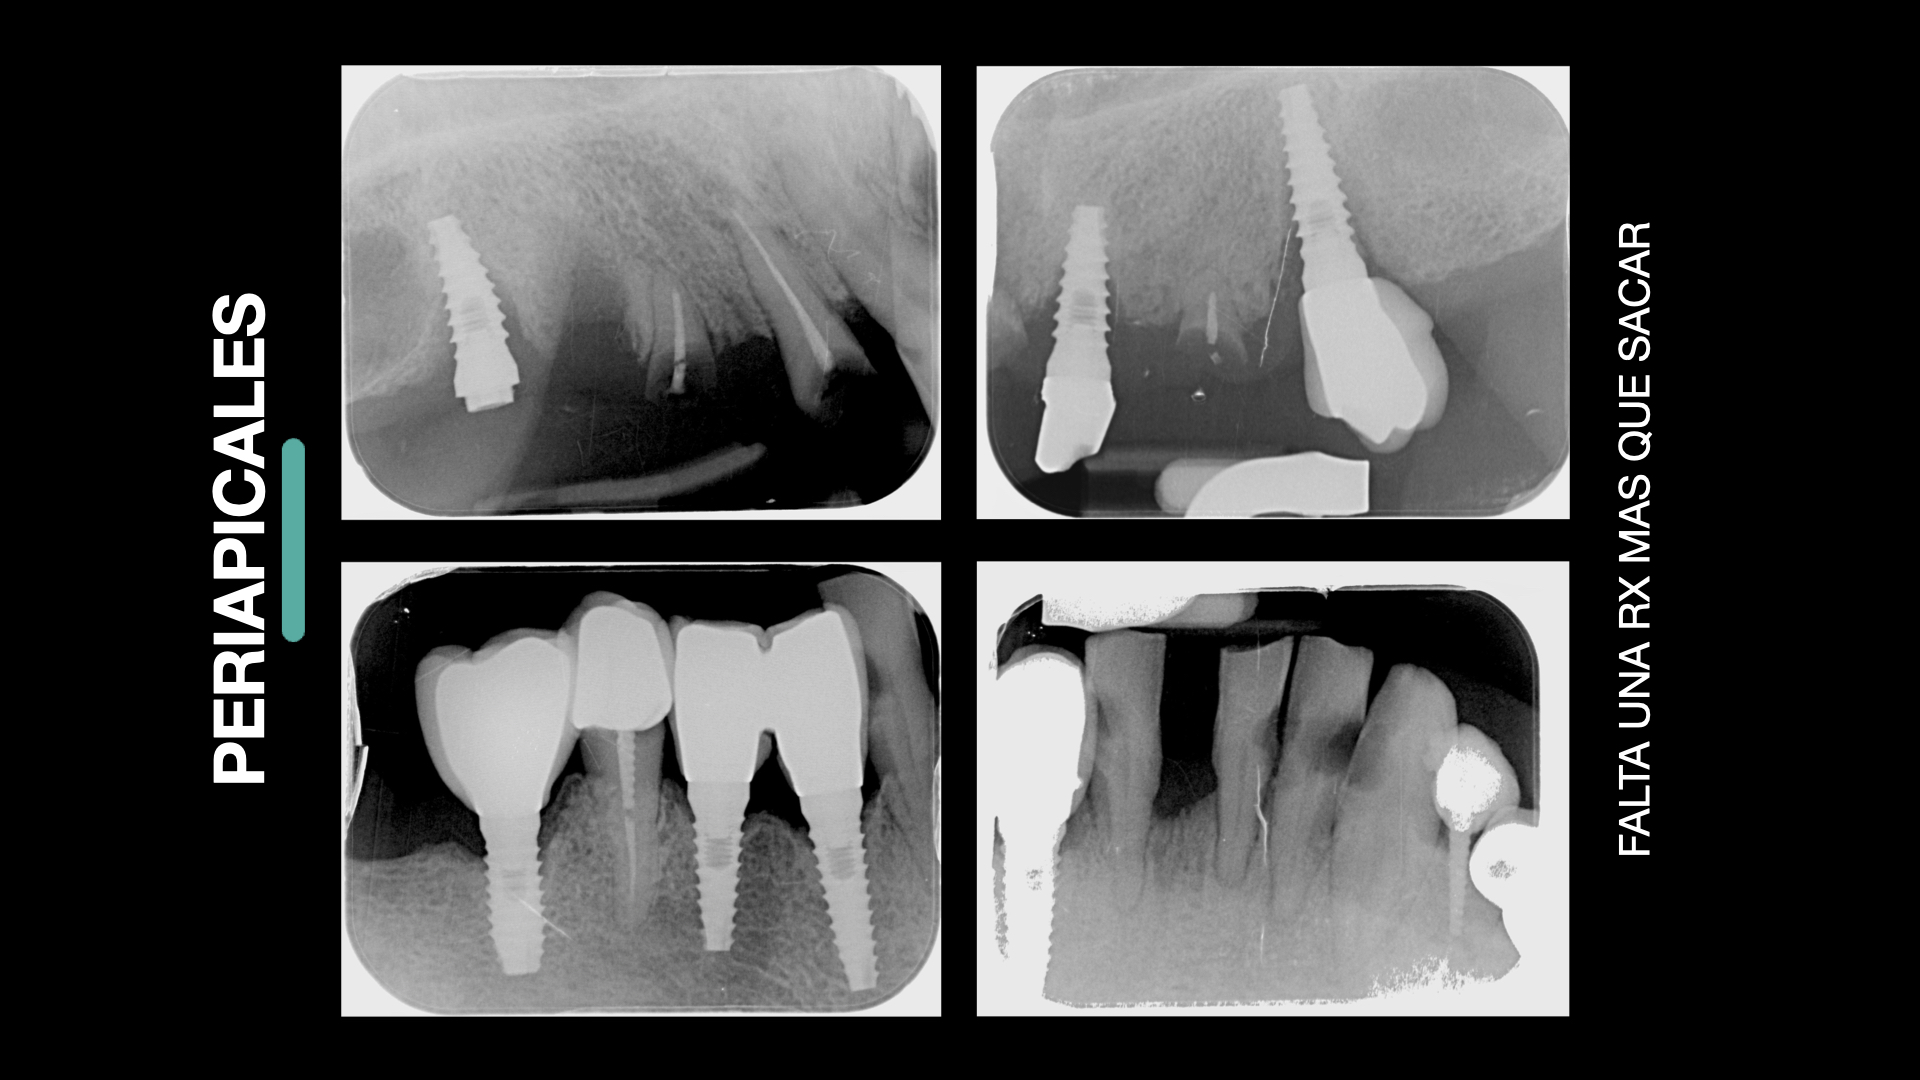

- Diagnóstico

- Planificación digital